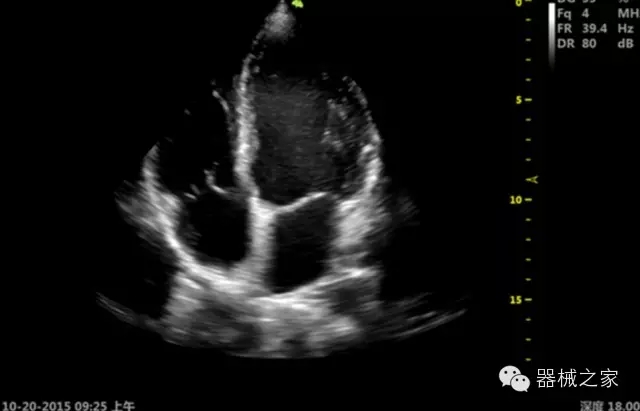

臨床圖片賞析

·移植S40高端臺式彩超高端平臺技術(shù),滿足超聲科腹部、淺表、婦產(chǎn)科、心血管、肌骨等應(yīng)用,提供超聲科完美解決方案;

·心功能綜合指數(shù)(TEI指數(shù)):用于左、右心室整體心臟收縮舒張功能評估的測量方法;

·全方位可調(diào)M型:有利于更好的觀察心腔大小及室壁階段性運(yùn)動(dòng)的異常情況;

·組織多普勒成像(TDI):TDI可定量評價(jià)心肌運(yùn)動(dòng),判斷是否有局部病變,還可評價(jià)早期的舒張功能;